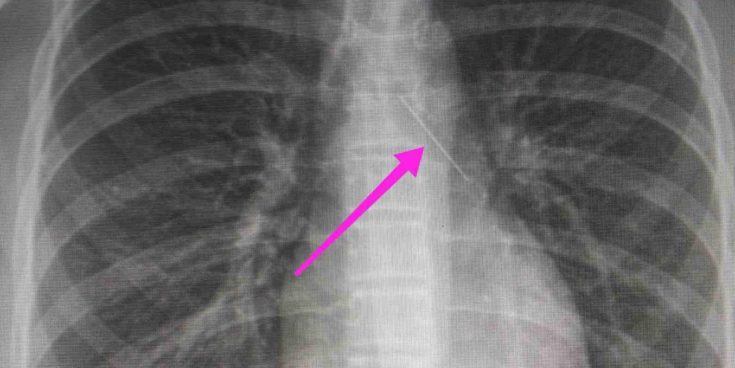

“Χθες 30/1/2022 στις 16:00 στο Τ.Ε.Π. του ΓΝΘ Ιπποκράτειο, προσήλθε ανήλικη συνοδευόμενη από τους γονείς της, μετά από αναφερόμενη κατάποση ξένου σώματος (καρφίτσα). Από την απεικονιστική διερεύνηση που πραγματοποιήθηκε με ακτινογραφία θώρακος αρχικά και ακολούθως με αξονική τομογραφία θώρακος, διαπιστώθηκε η ύπαρξη αιχμηρού μεταλλικού ξένου σώματος στην αναπνευστική οδό (αριστερός κύριος βρόγχος) και όχι στην πεπτική οδό.

Κατά την βρογχοσκόπηση διαπιστώθηκε η μετακίνηση και ενσφήνωση του ξένου σώματος στον δεξιό κύριο βρόγχο. Μετά οπό εργώδεις προσπάθειες ολοκληρώθηκε με επιτυχία η αφαίρεση αυτού. Η ασθενής ανένηψε πλήρως εντός της χειρουργικής αίθουσας. Η ασθενής μεταφέρθηκε για παρακολούθηση και νοσηλεία στη Γ’ Παιδιατρική Κλινική.